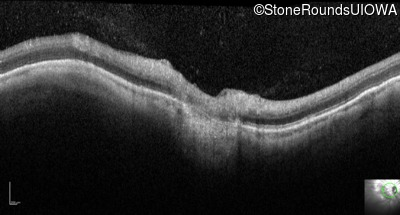

Infrared Fundus Photograph - Right - 20/100

Exemplar